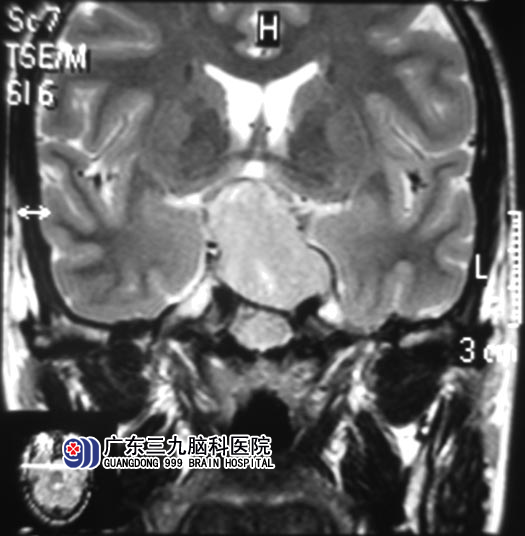

这回,凌先生不敢马虎。当地医院CT检查提示鞍区病变,广东三九脑科医院头颅MR见肿瘤大小约为27.5mm×25.4mm×34.9mm,视交叉受压稍上抬,考虑垂体大腺瘤可能性大。综合神经外科 鲁明主任初步判断可以行经鼻微创手术。http://www.999brain.com/

▲手术前